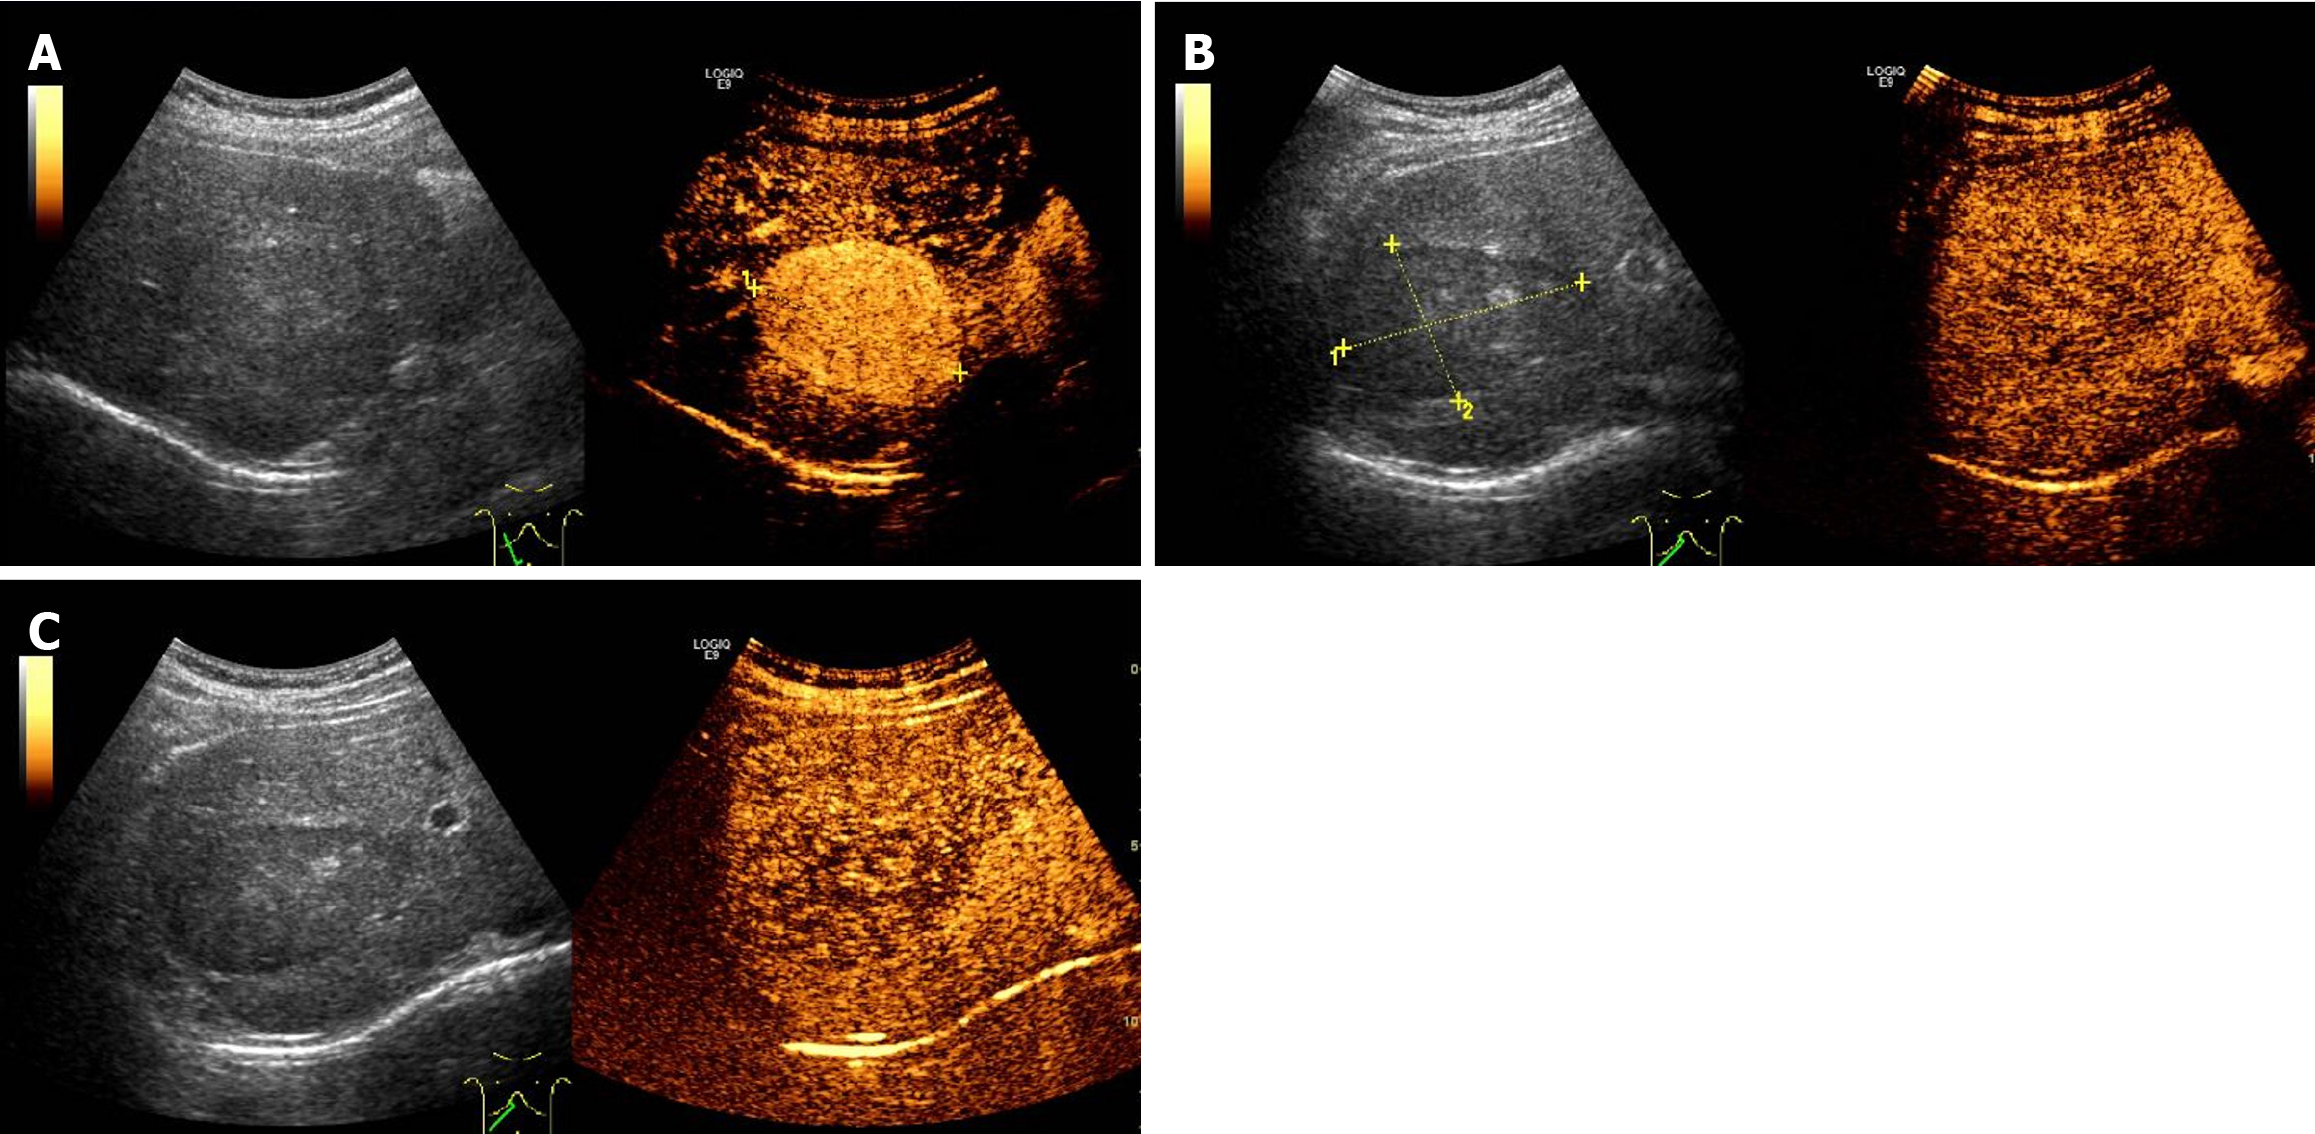

Figure 3 Enhancement patterns of contrast-enhanced ultrasound.

A: The lesion demonstrated a marked enhancement in the arterial phase; B: The lesion began to wash out during the portal vein phase; C: In the delayed phase, the lesion appeared slightly hypoechoic.